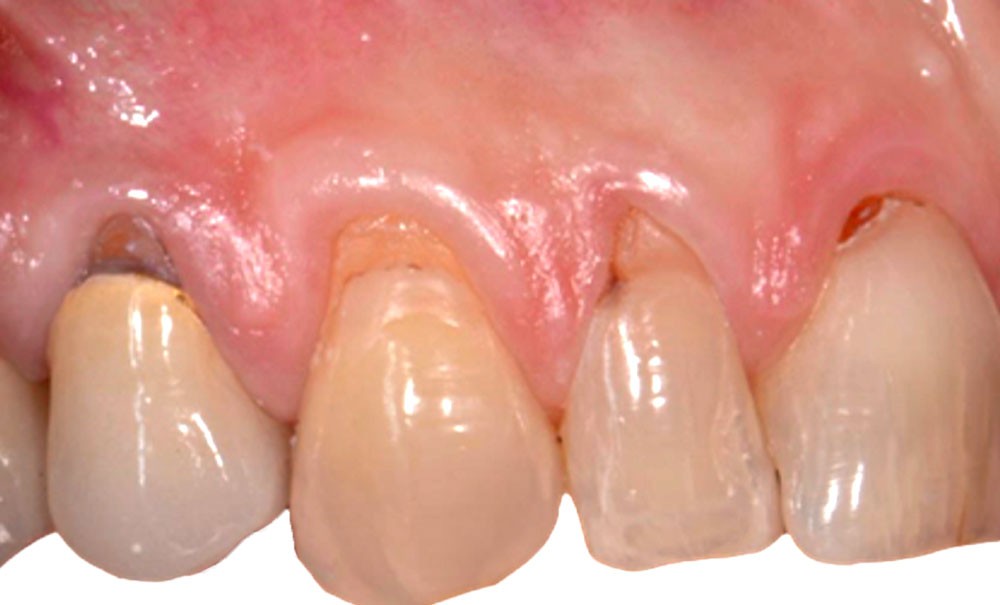

Le tracé d’incision papillaire, très précis, permet d’éviter les décharges. Il consiste à réaliser des incisions para-marginales obliques qui vont toutes être orientées en direction de la récession la plus sévère, ce qui permet d’obtenir un lambeau déplacé avec une légère rotation des papilles.

Le lambeau est ensuite décollé grâce à la méthode partielle-totale-partielle (« Split-Full-Split »). Les papilles chirurgicales sont décollées en épaisseur partielle afin d’obtenir un lit receveur et de stabiliser la position du lambeau au moment des sutures. Le lambeau est levé en pleine épaisseur jusqu’à la ligne de jonction muco-gingivale afin d’emporter le périoste, qui permet la vascularisation du lambeau. Enfin, dans un objectif de gain de laxité, le lambeau sera disséqué en demi-épaisseur dans la muqueuse alvéolaire. Cette dissection se fait en deux plans : un plan profond et un plan superficiel parallèle au lambeau muqueux. Le but est de permettre de repositionner le lambeau avec un minimum de tension.